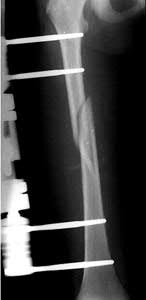

What is the most common type of malalignment after intramedullary nailing of distal 1/3 extra-articular tibia fractures using a infrapatellar approach when compared with plating?

The most common type of malalignment after intramedullary nailing of distal 1/3 extra-articular tibia fractures using an infrapatellar approach when compared with plating is valgus malalignment.

Fixation of distal one-third tibial shaft fractures can be successfully treated with either intramedullary nailing or plating. The literature describes advantages and disadvantages to both approaches, however intramedullary nailing has been shown to lead to increased rates of valgus malunion. Recent studies have shown that using a suprapatellar approach may decrease the incidence of valgus malalignement.

Vallier et al performed a randomized prospective study to compare plate and nail stabilization for distal tibia shaft fractures by assessing complications and secondary procedures. One-hundred and four patients were randomized to either reamed intramedullary nailing, or medial distal tibia plate fixation.

Primary angular malalignment was identified in 17 patients (16.3%). This included four patients treated with tibial plating (8.3%) and 13 patients treated with nails (23%, P = 0.02). Eight of these (7.7% of all patients) had malalignment between 6° and 10° of angulation. Valgus was the most common

angular deformity, accounting for 70% of angular deformity cases.

Avilucea et al. looked at the immediate postoperative alignment of distal tibia fractures (within 5 cm of the tibial plafond) treated with suprapatellar intramedullary nail (IMN) insertion compared with the infrapatellar technique. They found primary angular malalignment of ≥5 degrees occurred in 35 (26.1%) patients with infrapatellar IMN insertion and in 5 (3.8%) patients who underwent suprapatellar IMN insertion. They conclude suprapatellar IMN technique results in a significantly lower rate of malalignment compared with the infrapatellar IMN technique.